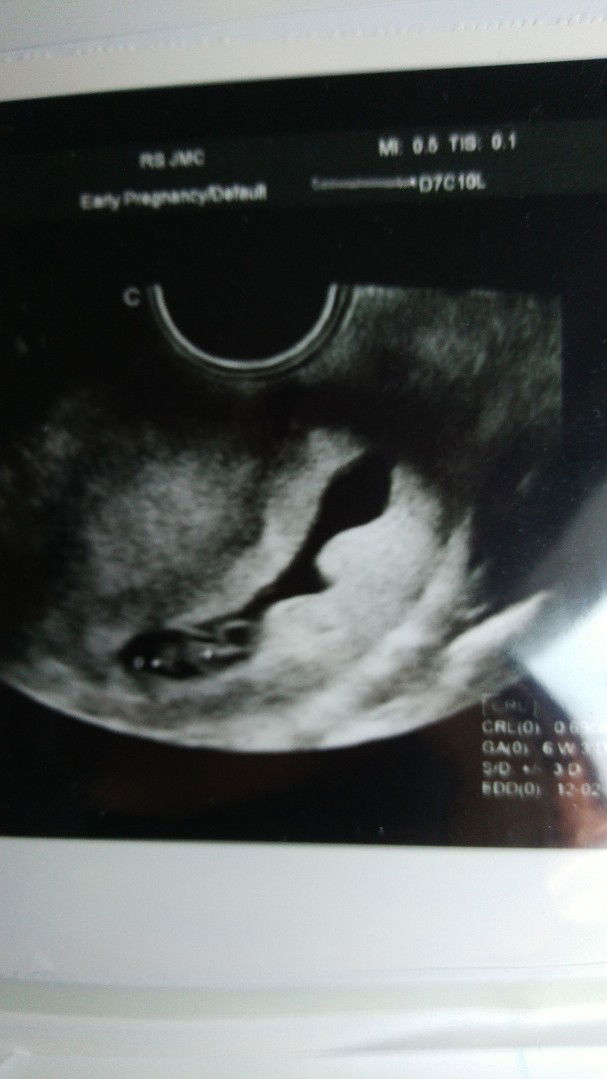

kantong kehamilan lonjong tidak beraturan

Bunda, mohon tanya, apa ada bunda bunda yang mengalami kasus seperti saya?setelah usg 6w kantong kehamilan saya terlihat lonjong tidak beraturan bentuknya, tp alhamdulillah janin sudah ada detaknya. Dokter menyarankan bedrest 5 hari dan mengurangi aktifitas g kerja dl bahkan solat di kasur saja. Padahal usia 4w bulat..Apa bisa kembali bulat ya bunda?:(